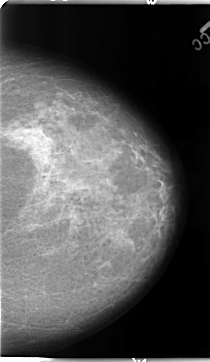

B_3103_1.LEFT_CC

LEFT_CC LINES 4704 PIXELS_PER_LINE 2720 BITS_PER_PIXEL 12 RESOLUTION 50 NON_OVERLAY

LEFT_MLO LINES 4688 PIXELS_PER_LINE 2856 BITS_PER_PIXEL 12 RESOLUTION 50 NON_OVERLAY